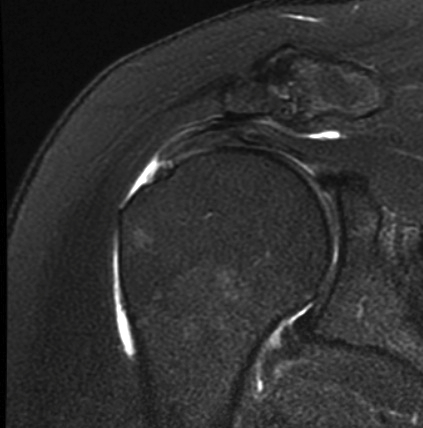

MRI

Look for

- supraspinatus / infraspinatus / subscapularis / long head of biceps pathology

- partial verus full thickness

- size of tear in coronal and sagittal planes

- retraction

- atrophy / fatty infiltration

Full thickness rotator cuff tears

Partial bursal sided tear Partial articular sided tears

Small full thickness rotator cuff tear of supraspinatus - retracted to footprint

Large full thickness tear of supraspinatus and infraspinatus tendon - retracted to midhumeral head

Massive rotator cuff tear of the supraspinatus and infraspinatus tendon - retracted to glenoid